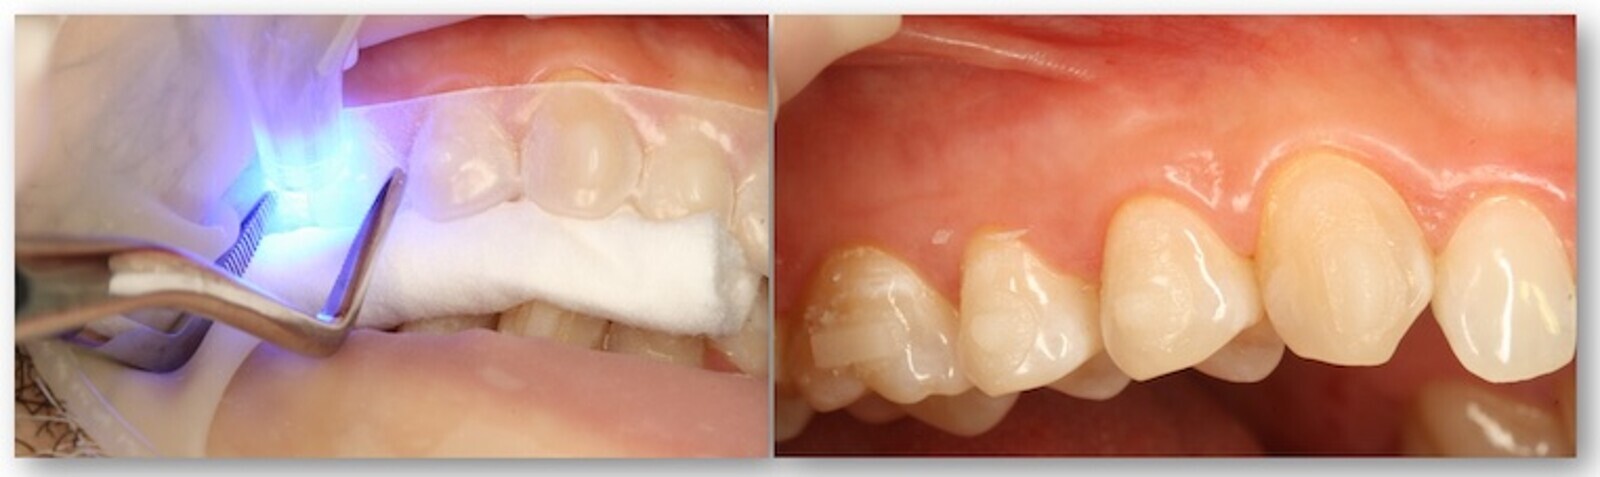

La colocación de ataches es un procedimiento sencillo y puede realizarse al mismo tiempo en toda la arcada o por segmentos (figura 52), cortando la férula de ataches con una tijera, en especial cuando el paciente presenta un alto índice de irregularidad y/o apiñamiento y/o superposiciones dentarias; hay que recordar que necesitamos: plena adaptación, presión y estabilidad.

Figura 52. La colocación de ataches es un procedimiento sencillo que puede realizarse al mismo tiempo en toda la arcada o por segmentos.

Cada maestrillo tiene su librillo, pero nosotros utilizamos la resina sin carga de la utilizada para adhesión de brackets, procurando presionar sobre el alineador con unas pinzas o un instrumento plástico. No colocar suficiente resina es un problema y yo, al menos, prefiero eliminar después los excesos con una fresa o una piedra tipo Arkansas muy fina (figuras 53 y 54).

Figuras 53-54. Es preferible usar una cantidad suficiente resina, ya que los excesos se pueden eliminar con una fresa o una piedra tipo Arkansas muy fina.